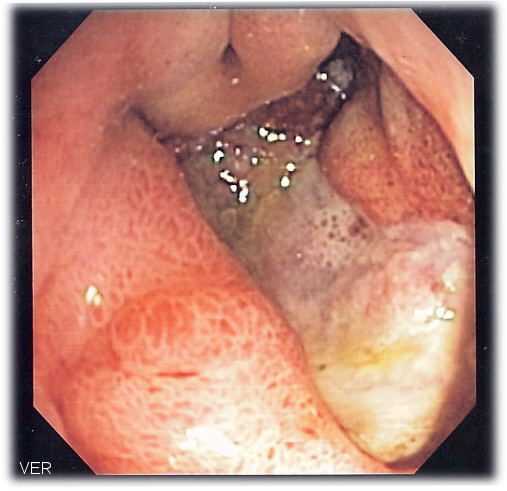

Gastric Carcinoma

Gastric carcinoma is the malignant proliferation of surface epithelial cells (adenocarcinoma) in the stomach.

Gastric carcinoma is sub-categorized as:

- Diffuse

- Intestinal forms

Laparoscopy of gastric carcinomas typically show a big, uneven ulcer with heaped-up edges characterizes the intestinal kind, which is more prevalent.

Gastric carcinoma typically affects the smaller curvature of the antrum (similar to gastric ulcer).

The majority of benign peptic ulcers are small (less than 3 cm), well defined, and encircled by radiating folds of mucosa.

Nearly seldom are duodenal ulcers cancerous (duodenal carcinoma is extremely rare).

Carcinoma is a differential diagnosis for peptic ulcers.

Gastric cancer can result in stomach peptic ulcers (intestinal subtype).

Malignant ulcers are big, asymmetrical, and have piled-up margins.

Biopsy is needed for definitive diagnosis.